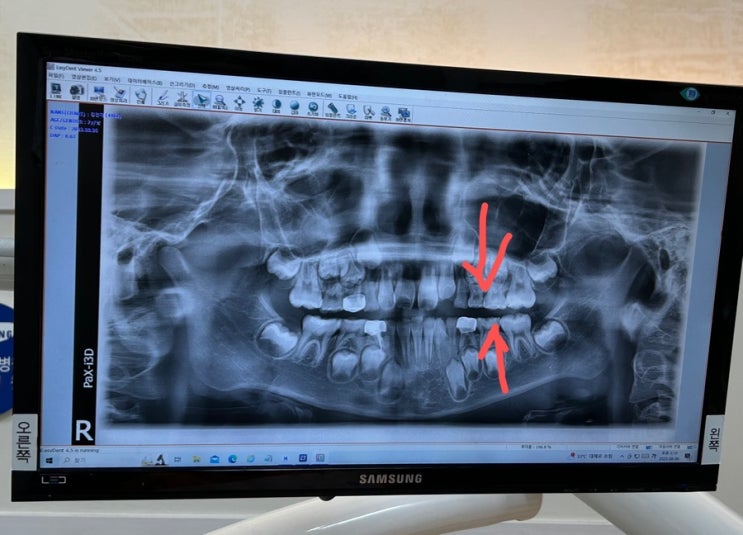

만7세반 아들 치과치료기록

둘째가 160일을 맞고.... 그동안 신경 좀 못써준 첫째 혼자서 하는걸 좋아해서 매일 집착적으로 해주던 치...